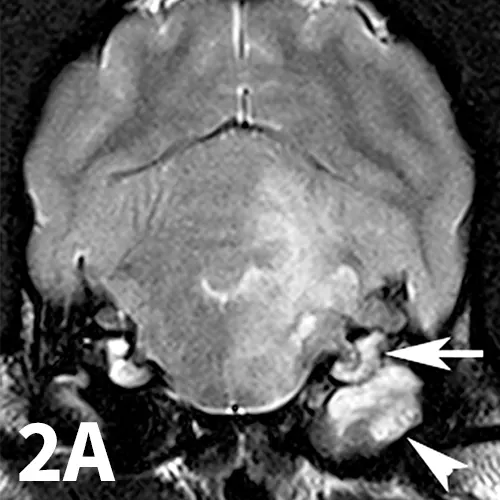

3. Trigeminal Neuritis and Idiopathic Trigeminal Neuropathy

A range of infectious and noninfectious inflammatory diseases can affect peripheral nerve branches. The most frequently recognized inflammatory entity in dogs affecting peripheral branches of cranial nerves is trigeminal neuritis or idiopathic trigeminal neuropathy (ITN).5 Affected dogs typically have an acute onset of clinical signs secondary to bilateral motor branch dysfunction of the trigeminal nerves. This bilateral involvement of the trigeminal nerve results in inability to close the mouth (drop jaw), difficulty prehending food, and drooling.5 About 33% of dogs have sensory involvement of the trigeminal nerve, and <10% have Horner syndrome or facial nerve dysfunction.5 While the underlying pathogenesis of this disease is not known, it is believed to be noninfectious and inflammatory in origin.5 Other causes can be excluded via MRI and cerebrospinal fluid analysis. Reported MRI findings include bilateral, subtle enlargement of the trigeminal nerve with associated T2 hyperintensity (Figure 3).2 The reported mean time to recovery is 22 days with <10% of dogs taking >6 weeks to recover.5 No treatment beyond assisted feeding is recommended for ITN. It may be necessary to try several food consistencies to determine what will be easiest for a particular dog to prehend; rarely, feeding tubes may be necessary. Team members who handle dogs (or cats) with any acute neurologic disease process, especially involving the trigeminal nerves or lower motor neuron system, should wear gloves, as rabies is a differential diagnosis, especially in unvaccinated animals.

Transverse postcontrast T1WI at the level of the caudal thalamus from a normal dog (A) and a dog with trigeminal neuritis (B). The trigeminal nerves are outlined in each study in red. The dog with trigeminal neuritis has grossly enlarged trigeminal nerves without an overt, identifiable mass.